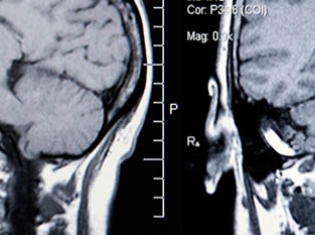

A specific kind of radiation called hypofractionated stereotactic body radiotherapy (SBRT) destroys nasal and other oral cancer tumors.

SBRT is a very precise technique that pinpoints the tumor without harming healthy nearby tissue. Dosing of this and all radiation treatments is key to success.

This therapy was used for tumors located inside and near the nasal cavity and around the sinuses, throat, tongue and other sites.